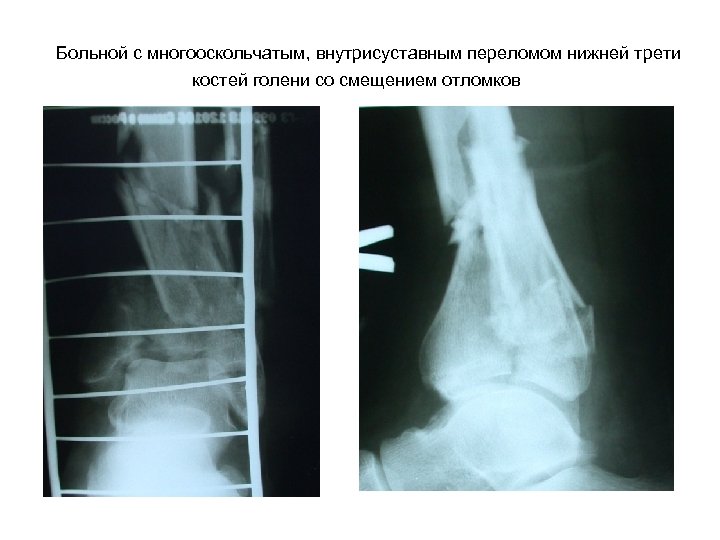

Больной с многооскольчатым, внутрисуставным переломом нижней трети костей голени со смещением отломков